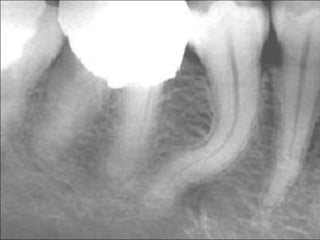

• Management of Curved Canals

A curvature of 20° in a narrow canal is almost

difficult to negotiate

whereas a curvature of 30° can be negotiated if

canal is wide.

Factor affecting success of negotiation of a curved

canal:

• Degree of curvature

• Flexibility of instrument

• Size of root canal

• Width of root canal

• Skill of operator

o Gradual curvature of the mesial canals in the

apical third.

o Acute curvature in the apical third.

o Curvature throughout the canal.

o Dilacerated root canal .

o S-shaped root canal.